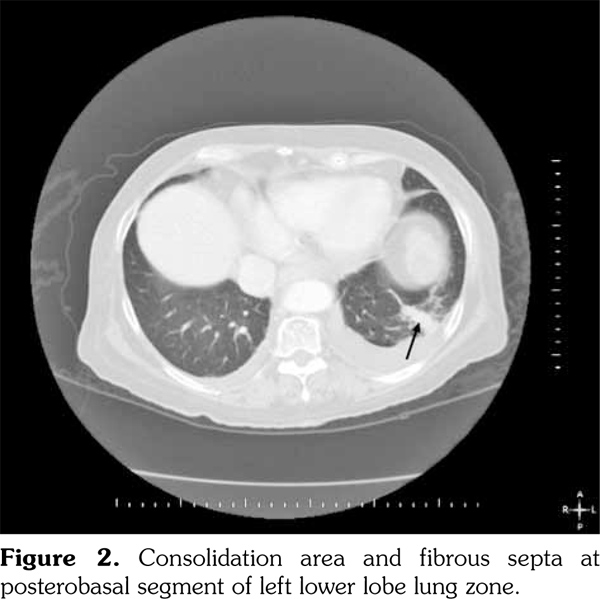

A 60-year-old female patient with no chronic disease except epilepsy which has been under control with oxcarbazepine and levetiracetam for 20 years applied to hospital. She received intravitreal bevacizumab injection (1.25 mg/0.05 mL) for age related macular degeneration at a private clinic and four days after this treatment, painful lesions emerged in her mouth accompanied with fever. She was admitted to the internal medicine clinic with these complaints and took diagnosis of febrile neutropenia. In spite of meropenem and amikacin treatment for four days, fever and neutropenia did not resolve; so, the patient was referred to our unit. On physical examination, her body temperature was 39.4 °C, multiple ulcers and white plaque lesions were observed in her mouth, and rales were present in the left lower lung zone compatible with pneumonia. X-ray revealed consolidation area with irregular borders at the middle zone of the left lung (Figure 1). The laboratory findings were as follows: white blood cells (WBC) 0.7 K/μl, neutrophils (absolute neutrophil count; ANC) 0.05 K/μl, platelets (PLT) 411 K/μl, hemoglobin (Hgb) 10.3 g/dL, C-reactive protein (CRP) 348.9 (0-5) mg/L, erythrocyte sedimentation rate (ESR) 101 mm/hour, procalcitonin 3.4 μg/mL (<0.05 μg/mL), total protein 5.9 mg/dL, and albumin 2.5 mg/dL. After obtaining the routine cultures, meropenem (3x1 g intravenous), vancomycin (2x1 g intravenous), liposomal amphotericin B (150 mg intravenous), and filgrastim (granulocyte colony- stimulating factor analog, 30 MU subcutaneous) were commenced. Thorax computed tomography showed pleural effusion accompanied by basal consolidation area and fibrous bands in the left lung compatible with pneumonia (Figure 2). On the fourth day of the treatment, patient’s fever and other clinical symptoms had not improved and laboratory results were as follows: WBC 1 K/μL, ANC 0.1 K/μL, Hgb 8.4 g/dL, PLT 535 K/μL, CRP 144 mg/L, ESR 140 mm/hour, and procalcitonin 2.24 μg/mL. Patient’s sputum culture yielded Stenotrophomonas maltophilia susceptible to trimethoprim/sulfamethoxazole and levofloxacin. Previous antibiotics were discontinued and trimethoprim/sulfamethoxazole and levofloxacin were started. Besides antibiotic therapy, anti-epileptic regime was maintained. The infectious agents which can cause neutropenia were also excluded. Antinuclear antibodies were detected as positive (++) by immunofluorescence assay at 1/100 titration and homogenous pattern. Also, anti-double stranded deoxyribonucleic acid was positive (+++) by immunoblotting techniques. In urinalysis, proteinuria was detected. Following the detection of protein in urinalysis, protein in 24 hour urine was measured as 735 mg. At the fifth day of the treatment with trimethoprim/ sulfamethoxazole and levofloxacin, patient’s body temperature returned to normal and clinical symptoms improved. Laboratory results were as follows: WBC 7.9 K/μL, ANC 4.5 K/μL, Hgb 8.5 g/dL, PLT 205 K/μL, CRP 10.5 (0-5) mg/L, ESR 36 mm/h, procalcitonin 0.08 μg/mL, blood urea nitrogen 27 mg/dL, and creatinine 0.8 mg/dL. An evaluation of kidney biopsy performed due to significant proteinuria revealed mild staining with immunoglobulins and complements. Kidney biopsy was found compatible with class III + class V lupus nephritis.